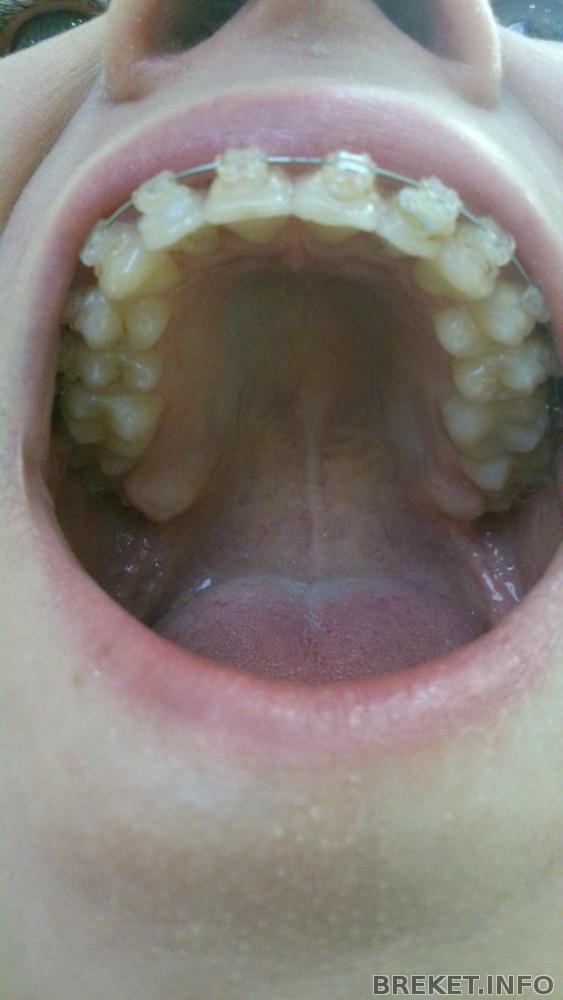

Polyaa последнее фото где ВЧ это свежее? там видно что дуга кривая у единичек.

Skoll, нене, которая фото ВЧ в комменте - это самое начало лечения, сейчас все по другому. Да, меняет, ставит толще, ну не каждый раз, месяцев через 3 выходит новая дуга как раз)

Я вижу что у тебя немного расширился зубной ряд на ВЧ, и дуга вроде сейчас стоит не круглая? с центром да, беда, но ровняться на то, что было ДО лечения не стоит, т.к. тот ровный центр был при кривых зубах. Надо узнать у орта когда он планирует начать заниматься центром.